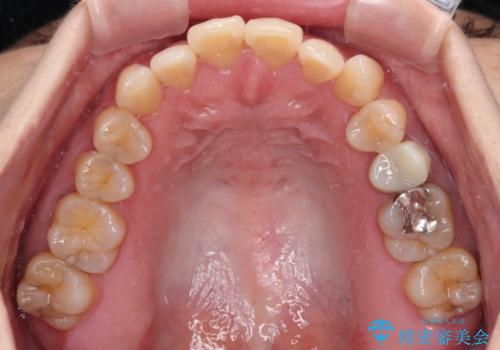

- 前歯のデコボコと口元の突出感を気にして来院された患者様です。

上下前歯がくちばしのように突出していたため、上下左右の第一小臼歯4本を抜歯し、ワイヤー装置にて矯正治療を行うこととしました。

上顎骨に対して下顎骨がやや前方位に位置しているため、歯肉退縮を回避するために下顎前歯をあまり内側に移動させることができない状況でしたが、十分に口元の突出感を改善することができました。